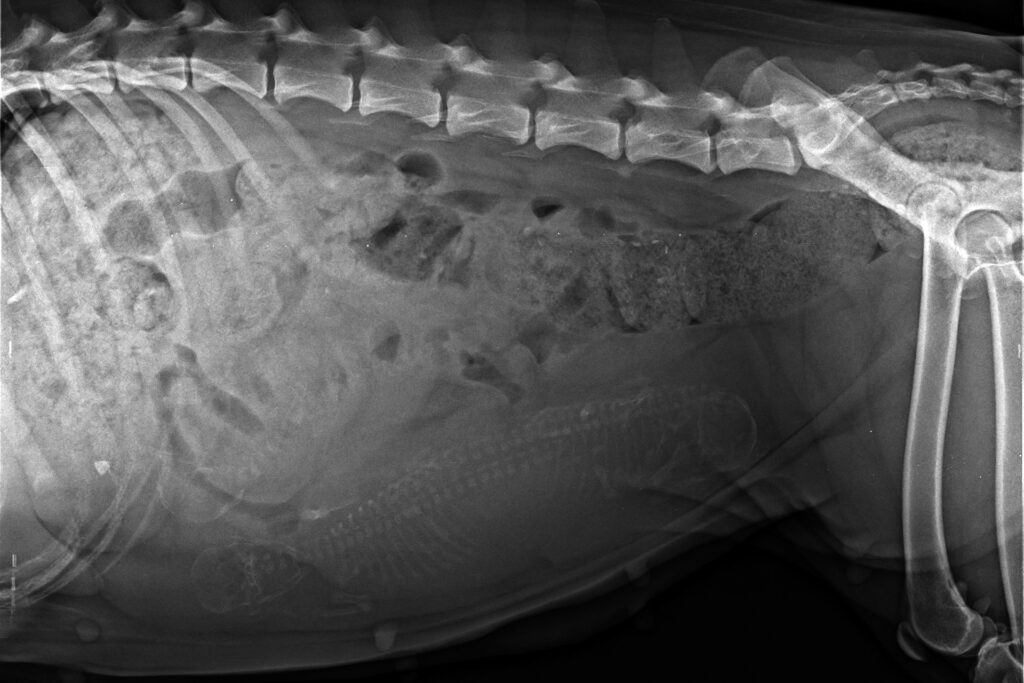

Today’s X-ray turned out a bit astonishing: The vet saw no more than 3 puppies, well grown and neither to big nor too small for little Opra. Maybe there is another Puppie hidden in the shadow of the guts, but we do not bet on that. At the turn of […]